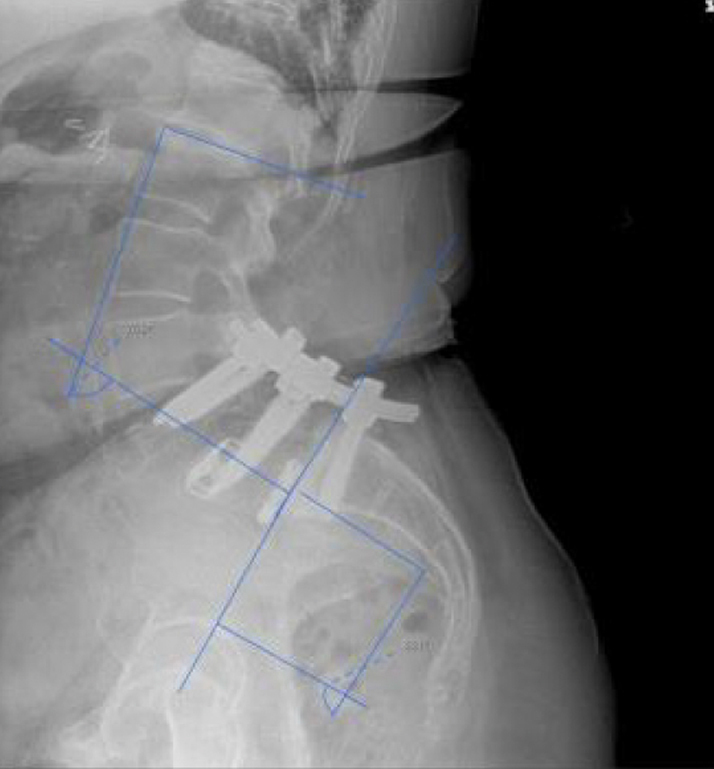

- High lumbar lordosis (77°) & pelvic incidence (86°)

- L4-5 & L5-S1 MIS transforaminal interbody fusion, November 2017

- Revision open L4-S1 fusion for pseudoarthrosis and hardware loosening, March 2019

- Bilateral SI joint fusion using the iFuse 3D™ Implant System, August 2020

Post-op:1

- Post-op resolution of bilateral SI joint pain.

- CT of lumbar spine at +2 years post-op shows confirmation of the SI joint fusion.